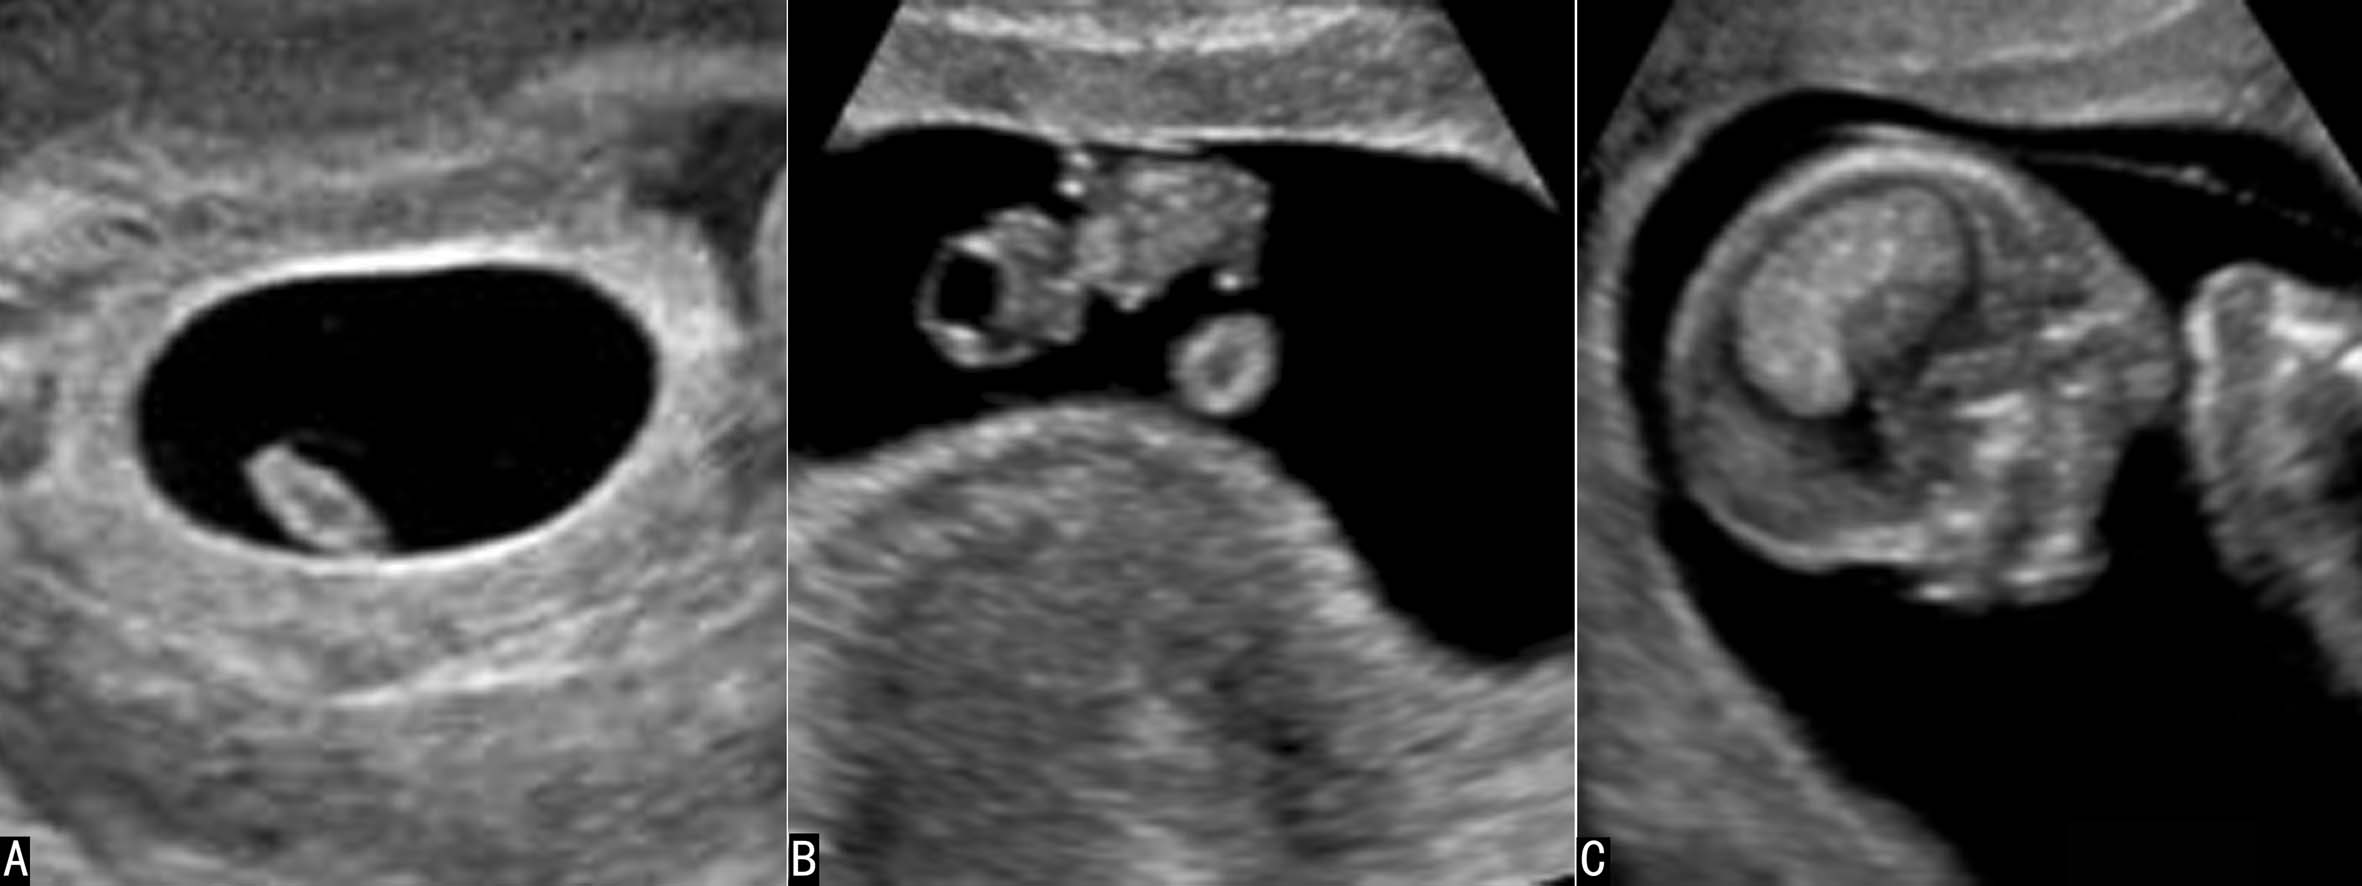

妊娠早期的羊水在声像图上显示为纯净的无回声区,胚胎或胎儿及脐带在羊水无回声区内显示得非常清楚(图1),直至中期妊娠的后期超声显像检查羊水内有时可以显示少量较低的点状回声(图2)。

图1早孕期羊水显示

妊娠早期超声显像检查显示孕囊时所显示的无回声区并不是羊水,而是胚外体腔内的液体。约在妊娠第6周、妊娠囊直径达到15~20mm时,羊膜腔逐渐增大,第6~8孕周时超声显像检查有时可以显示妊娠囊内的羊膜回声,将妊娠囊分为两部分,包绕胚胎周围的部分为羊膜囊,其内部为羊水,卵黄囊存在的部位是胚外体腔。此后伴随羊膜腔的逐渐增大、胚外体腔逐渐缩小至消失,超声显像检查所显示胎体周围的无回声均由羊水形成。